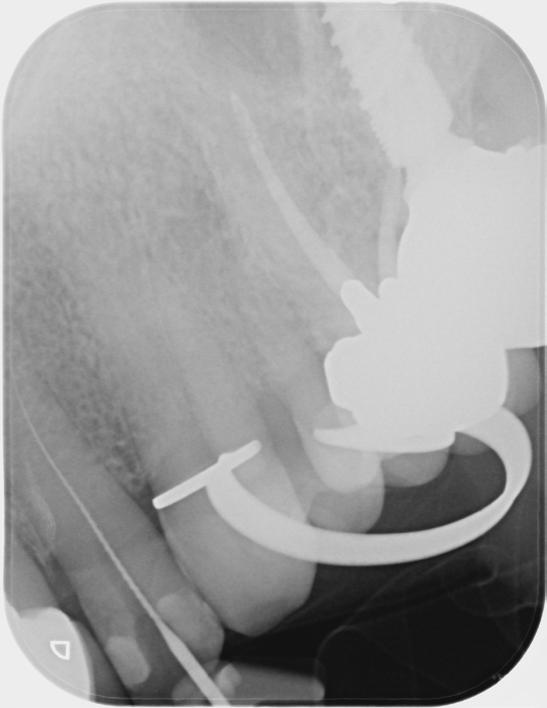

Based on the clinical and radiographic findings, tooth 22 was diagnosed as necrotic with a possibly infected root canal system (RCS), pulp canal calcification and primary acute apical periodontitis due to decay, cracks and restoration breaking down. An endodontic investigation procedure was planned to determine whether the 22 was suitable for further restoration. While the treatment was supposed to be straightforward initially, it progressed to become very complex surprisingly. This was due to separation of a size-10 H-file in the root canal of tooth 22.

The instrument separation was first noticed after taking the initial radiograph to establish the working length. It probably happened due to the patient biting inadvertently on the file during x-ray exposure. As our patient was a bruxer, his bite forced the file deeper in the

severely calcified root canal. The file was now firmly stuck inside the root canal. Despite trying to gently retrieve the file, it broke at junction of the cutting surface to the shank. Bypassing and/or retrieval procedures were planned and performed by using hand files, rotary files and Satelec ultrasonic tips in three different sessions, each one almost three hours long. Rotary files were used mainly as adjunctive instruments.

Taking advantage of rotary files made of a heat-treated alloy with minimal cutting efficiency, designed in a way to scrape rather than cut the dentin, enabled me to safely enlarge the space made by the hand files. This technique also participated in less frequency and chance of breaking more files next to the broken file.

Finally, the broken file segment was removed with braiding barbed broaches around the file. Notably, the patient patiently cooperated all throughout the treatment.

I had a thorough discussion with the patient about the reasons why this incident happened. Even though I could have simply pointed out a severely calcified root canal or a heavy bite to be responsible for the incident, I concluded that the patient’s occlusion should have been assessed carefully during case assessment in order to set preventive measures, which in turn could have potentially saved the patient and I from all the consequences.

Take home message - ALWAYS check your patient’s occlusion during the first examination/ consultation session. It will save you a lot of money!

Fig.1 File got stuck (22/09/2023) Fig.2 File fractured (22/09/2023)

Fig.4 Cut the file deeper (22/09/2023)

Bypassed to WL (12/10/2023)

And even deeper (12/10/2023)

Fig.3 Made space coronally (22/09/2023)

Fig.6 Rotary files used (12/10/2023)

Fig.8 Finally retrieved the file (12/10/2023)